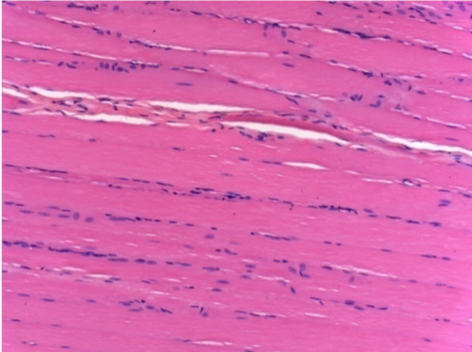

Через 1 місяць після ін'єкції Ендопілу 0,1 мл у правий претибіальний м'яз.

Те, що видно на знімках чорним кольором, не є некрозом, як можуть собі уявити деякі науковці!

Насправді, слід взяти до уваги 4 висновки